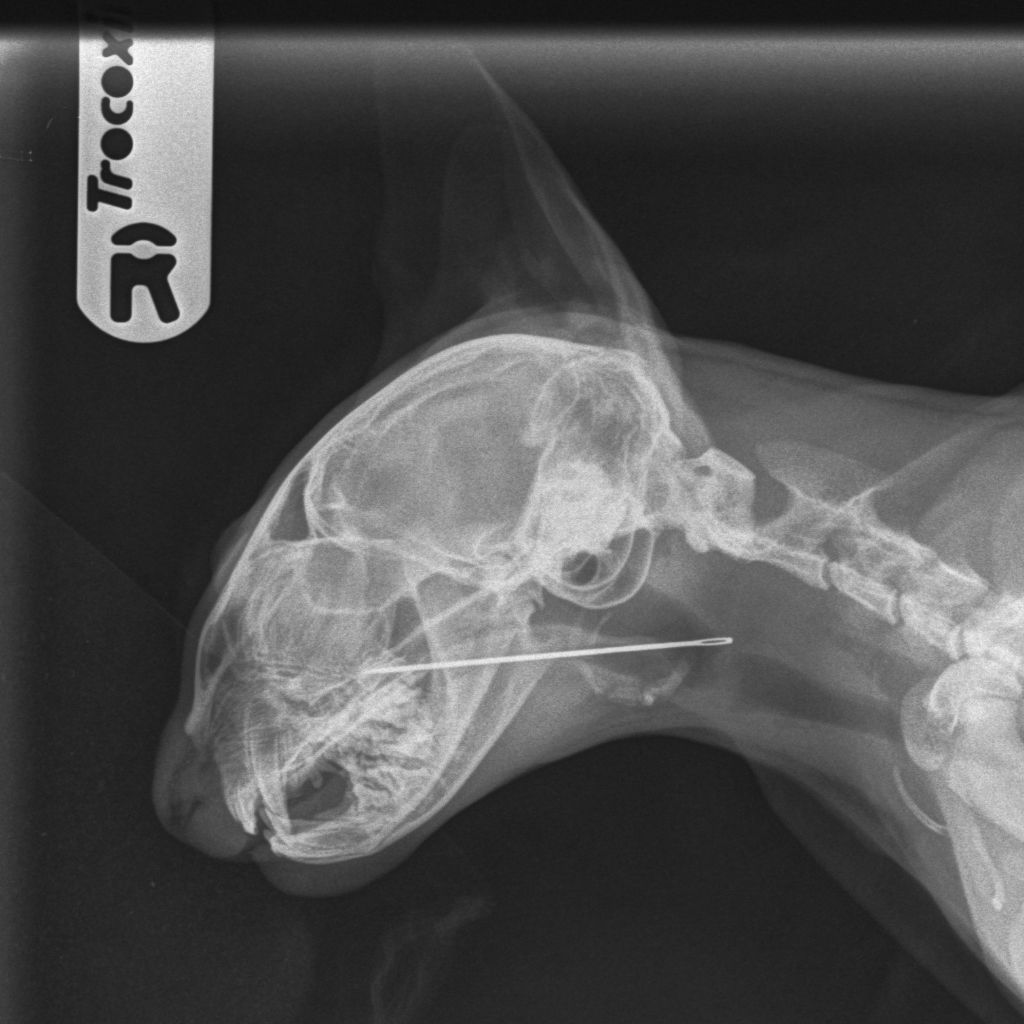

Ember’s owners brought her to the clinic after noticing she was coughing. Upon examination by Dr Gethin Edwards-Jones, supported by Yasmin (Registered Veterinary Nurse) and Rachael (Veterinary Care Assistant), the team identified the foreign object. An X-ray confirmed the needle’s location, and Ember was sedated so the veterinary team could carefully remove it.

Dr Gethin Edwards-Jones added: “Cases like Ember’s show how important it is to seek veterinary advice promptly when something seems off. A sewing needle in the throat can cause serious complications, but thanks to quick intervention and teamwork, Ember is now on the mend.”